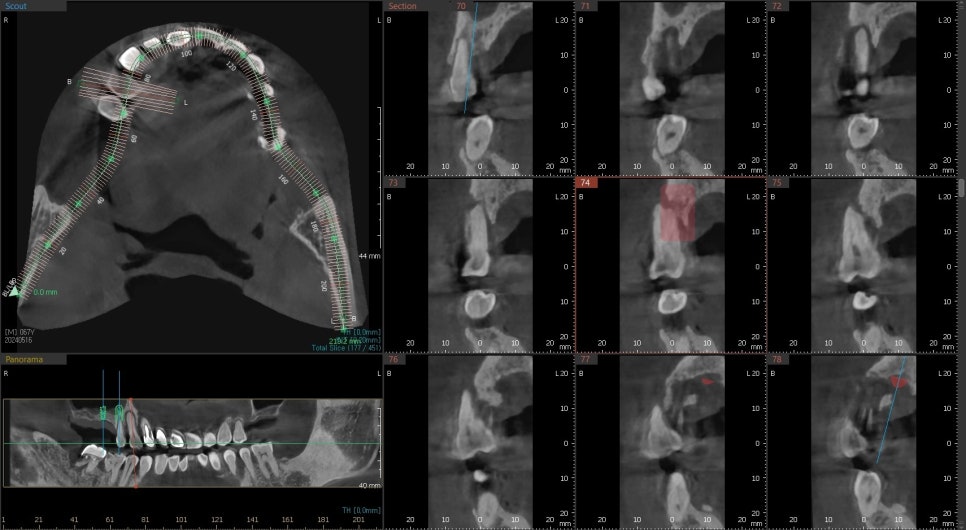

1차 수술

사진에 표시된 부분은 광범위한 염증으로 인해 즉시 임플란트 수술은 어려웠고

나중을 위해 뼈이식을 먼저 한 후 나중에 수술하는 계획을 세웠습니다.

앞서 상악동 거상술이라는 술식으로 양쪽 어금니에 들어갈 임플란트 부분의 공간을 확보했습니다.

사진과 같이 수직적으로 접근하여 필요한 양만큼 치조골 이식술을 시행했습니다

처음 1차 수술 때 발치와 주변에 처치를 했지만

기다림의 시간이 무색하게도 추가적인 치조골 이식이 필요했습니다.

다행히 기존의 환자분의 뼈는 회복이 되어 임플란트 수술과 동시에 추가 뼈이식을 시행했습니다.

2차 수술 후 엑스레이 사진입니다.

최종 보철물까지 진행은 아직 안 되었지만